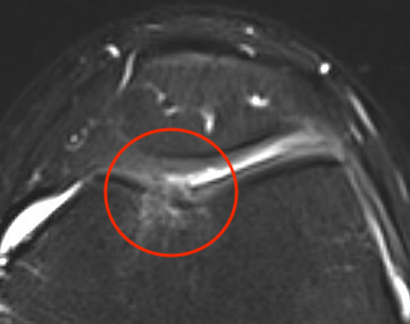

MRI

Microfracture of trochlea chondral defect

AMIC procedure of a full thickness patella lesion